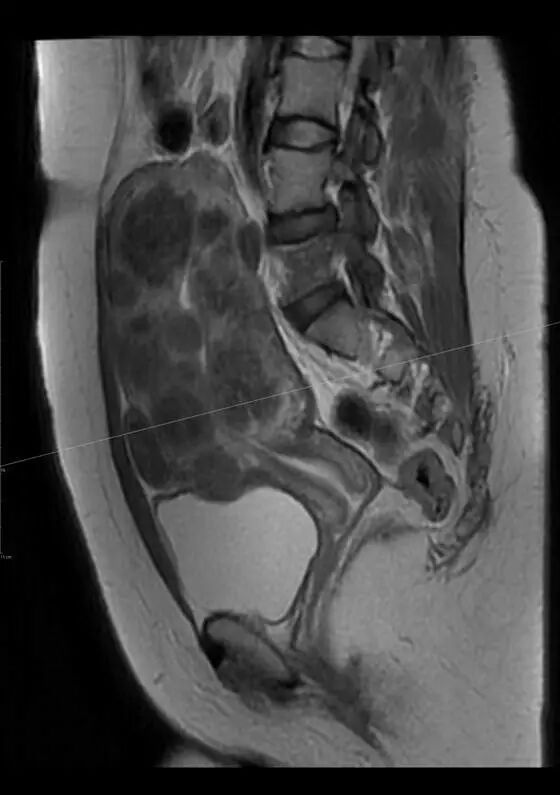

图 4 为 34 岁女性有严重的月经过多和贫血,腹部 MR 示一巨大单发 30*20 cm 肌瘤。医生建议其接受子宫切除术,但她选择肌瘤栓塞术。术后肌瘤体积减小 60%,症状得到控制

图 5 为 MR 示 29 岁女性多发子宫肌瘤,已无法手术切除肌瘤。而肌瘤栓塞术可以保留子宫和生育能力。患者术后 12 个月后怀孕